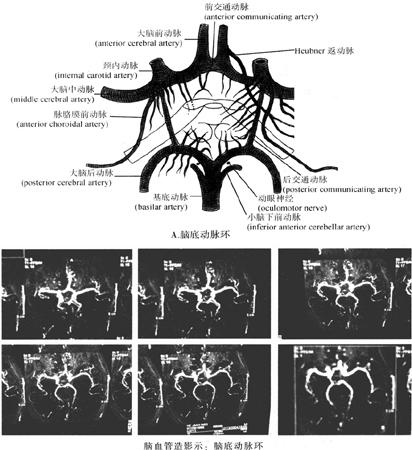

脑血管分布的特点是:主要的动脉都在脑底,而主要的静脉都在脑的表面。脑的血供主要由颈内动脉(internal carotid artery)及由锁骨下动脉(sabclavian artery)发出的椎动脉(vertcbral artery)及基底动脉(basilal artery)即椎基底动脉系统来完成(图12-78)。

图12-78 脑的动脉(A、B)

5.脑底动脉环(图12-82) 也称大脑动脉环(cerebral arterial circle)、基底动脉环(basilar arterial circle)、动脉环(arterial circle) 或环状动脉(circular artery)等。此环由Thomas Willis于1664年首先描述,故常称为Willis环。

Willis氏环的组成目前有两种说法:一是由大脑前、中动脉的近侧段、单一的前交通动脉、左右颈内动脉、左右后交通动脉及左右大脑后动脉共同组成;二是认为此环由大脑前、中、后动脉近侧段及前、后交通动脉组成。按颈内动脉行程分支情况及解剖所见,以第一种情况较为多见。

Willis氏环的存在对脑血液循环,尤其对脑血流量的调节方面有重要意义。许多研究证明,人在正常安静状态下,Willis氏环两侧的血压几乎相等,组成环各部的血流不混杂,即一侧的动脉血流不经过交通动脉流入另一侧,甚至同侧的颈内动脉系与椎-基动脉的血流也不相混。颈内动脉造影时,椎-基动脉分支多不显影;椎动脉造影时,颈内动脉分支也不显影,相关情况足以说明颈内动脉系和椎-基动脉系在正常情况多不相混,只是在头、颈、上肢运动时,将影响颈内动脉和椎-基动脉而引起血流量增加或减少,此时可通过Willis氏环进行调节达到始终保持脑血流量的平衡,或当某一血管受阻或发育不良时,Willis氏环也能起到代偿的作用。由此说明Wills氏环是在生理情况下脑侧支循环的一个主要潜在结构,但在病理情况下Willis氏环能在多大程度上发挥代偿作用,其中重要的条件是取决于后交通动脉的发育与变异情况。如一侧颈内动脉阻塞时,若后交通动脉发育不良或其他变异,其侧支代偿作用是有限的。

从Willis氏环的组成可见它有闭锁型和开放型两种。闭销型:组成的血管完整,中国人占96.3%(1205例),Solnitzky及Mccormick为40%~53.8%(1500例);开放型:中国人约占3.7%,其中主要表现在后交通动脉的缺如以及少数前交通动脉和大脑前动脉近侧段缺如(图12-82)。

据临床观察,颅内动脉瘤多发生于Willis氏环,并认为该环有变异者,其动脉瘤的发生率较正常高达2倍,其中发生于大脑中动脉分叉者20%,发生于前交通动脉者约30%,发生于靠近后交通动脉起始的颈内动脉者占20%~30%,发生于基底动脉接近分出终支处15%,尚有15%散发于周围血管。这可能与由于结构上的缺陷,可使侧支循环的血流有较大的机械性阻力有关。